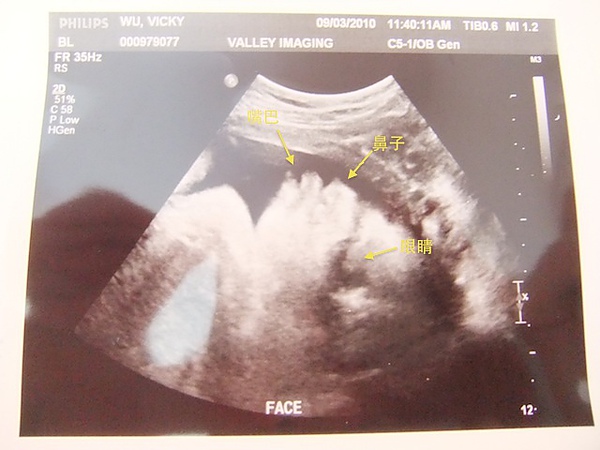

這次的超音波體驗我們很滿意,因為檢驗師很花時間的幫我們照超音波,還細心的把Jelly加熱過,所以Jelly在肚子上是溫溫的很舒服,檢驗師一部份一部份的照,看得很仔細,左右手腳,甚至內臟,都一一的花時間照給我們看,前前後後我們花了20分鐘在照超音波,總共拍了20多張超音波照片,妹妹一切健康正常,只是~麻麻我腹腔空間太小,妹妹的臉在骨盆腔內被擠壓到變形,我們既覺得可憐也覺得好笑!

妹妹的側臉

妹妹的正面~整個被擠壓到變形,麻麻我骨盆腔太小了,Sorry~幸好助產士說,不用擔心,生完之後就會彈回原形!